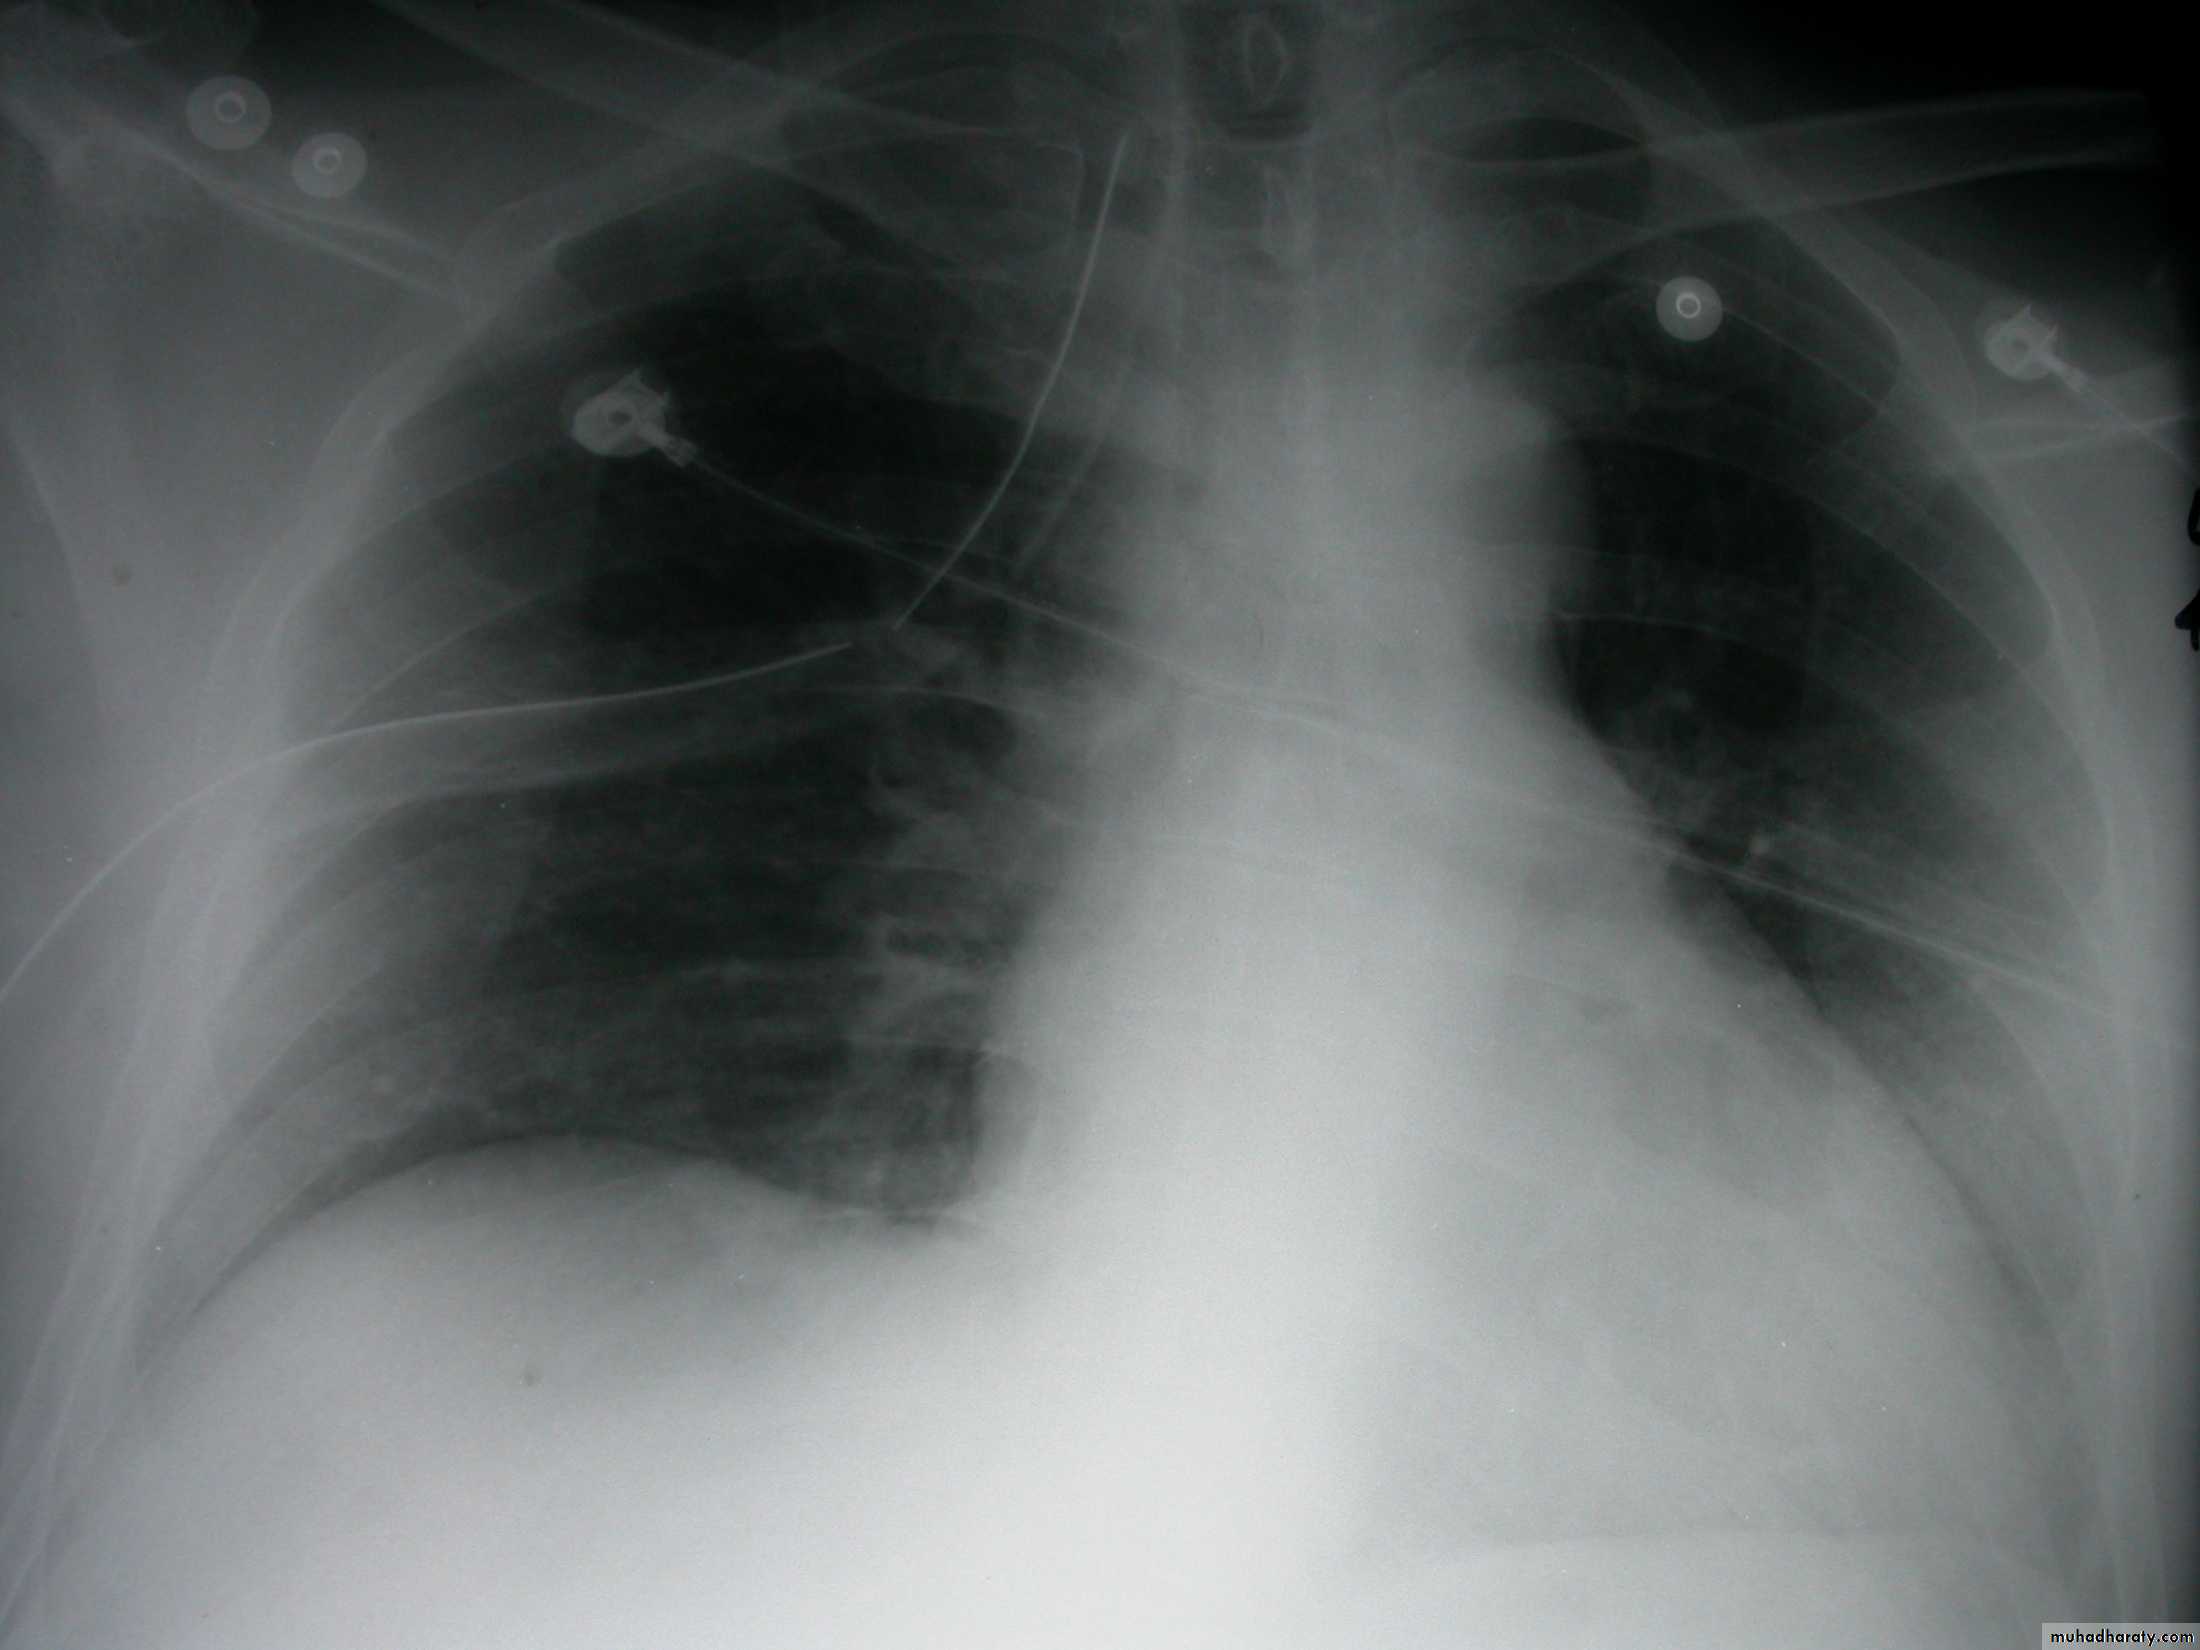

Empyema

Recurrent or malignant Pleural effusion

History: dyspnea, weight loss, dehydration with poor immunity

History; too shy to take of his shirt in the pool!

What is the difference?

Differential diagnosis?